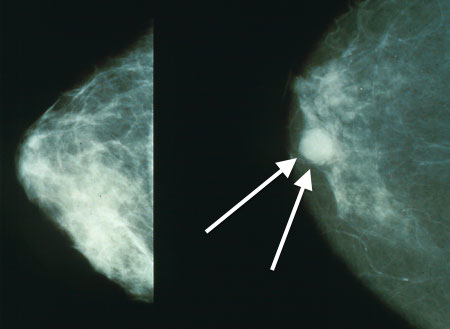

Ductal carcinoma in situ (DCIS) is the term for malignant ductal cell growth that does not involve basement membrane invasion.

Although ductal carcinoma in situ (DCIS) often shows up as calcification on mammography, it rarely results in a malignancy.

Mammographic calcifications can also be associated with benign disorders such as fat necrosis, sclerosing adenosis, and fibrocystic changes.

Biopsy of calcifications is often necessary to distinguish between benign and malignant conditions.

The comedo type of ductal carcinoma in situ (DCIS) is distinguished by high-grade cells with necrosis and dystrophic calcification in the core of ducts, whereas histologic subgroups of DCIS are based on architecture.